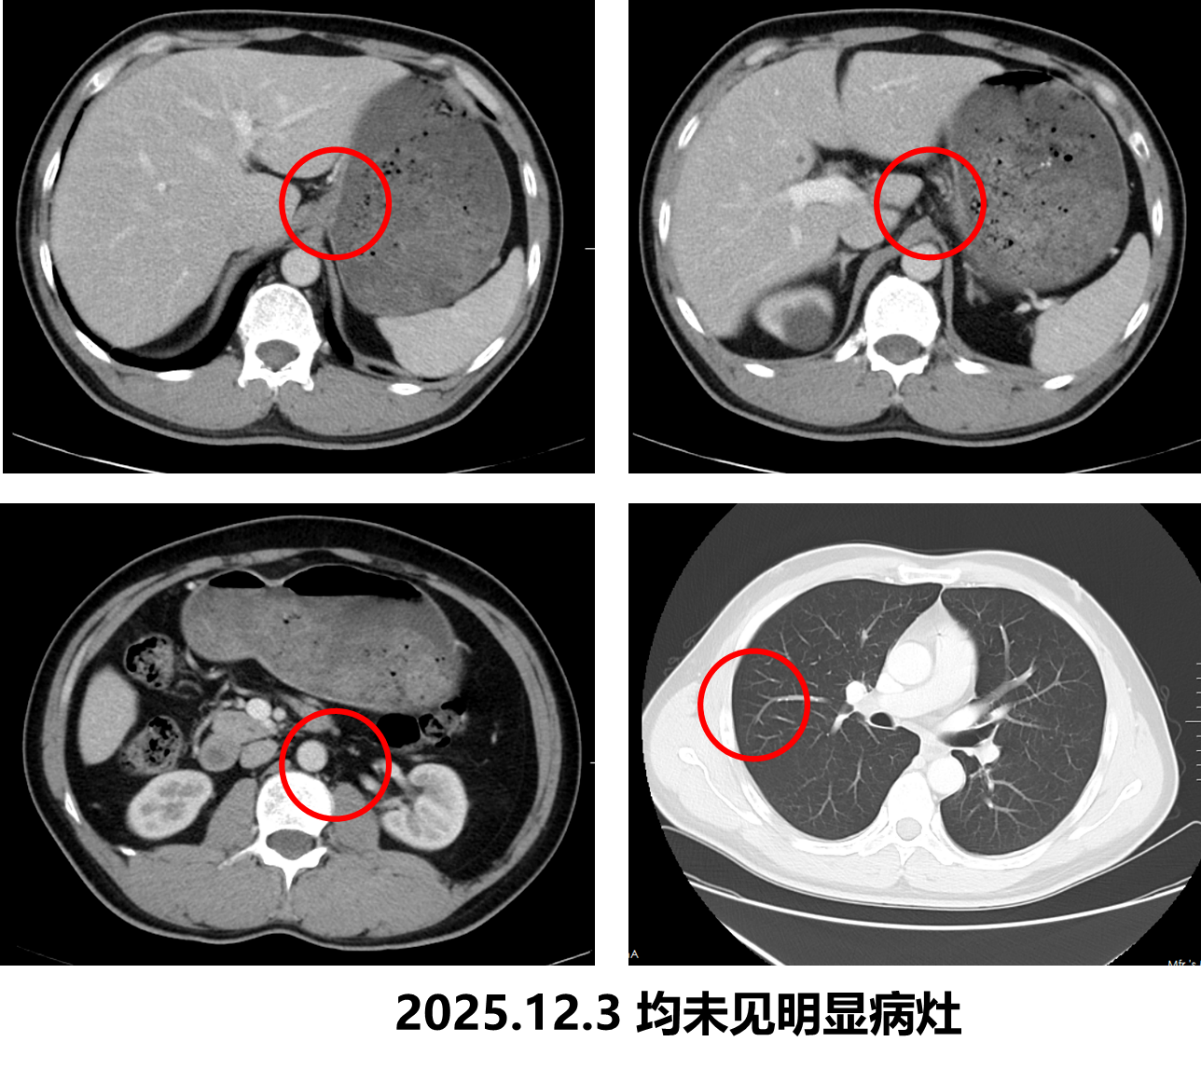

• 2025.12.3 复查CT:胃底贲门部胃壁稍厚大致同前,肝胃间隙、腹膜后小淋巴结同前。双肺纤维灶大致同前。